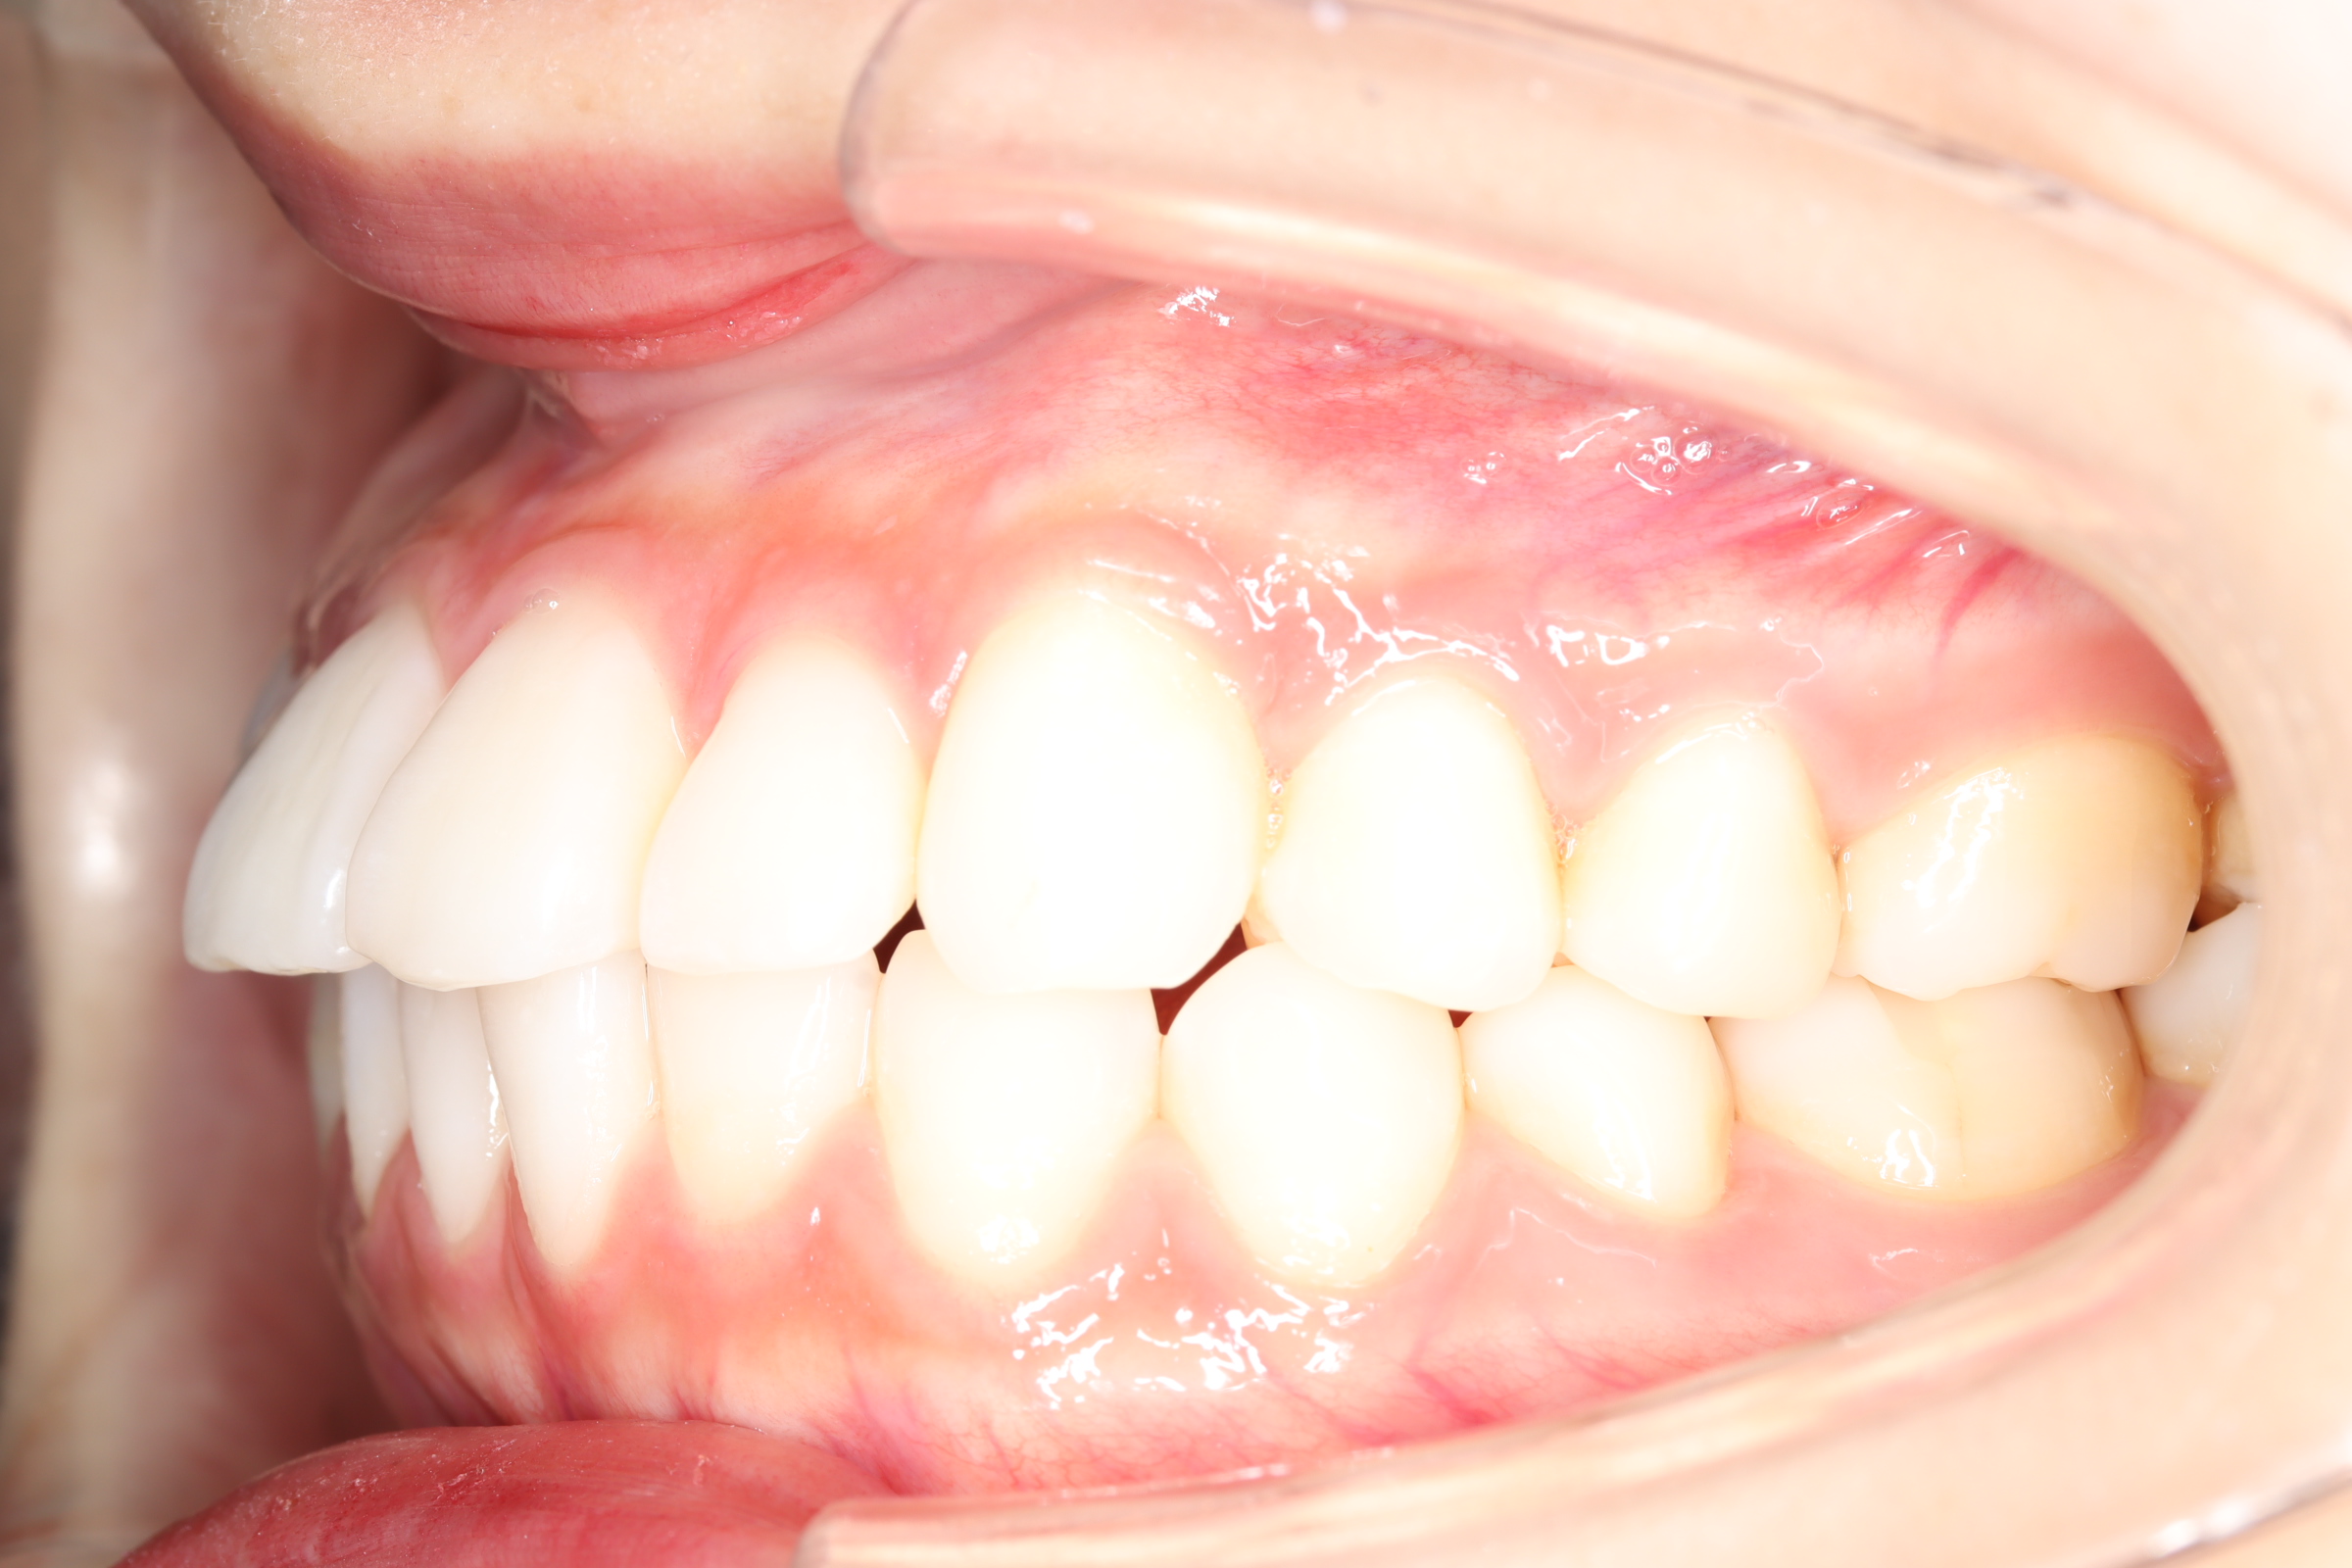

口腔内とラテラルセファログラムの変化

![]() | ![]() | ![]() |

| ↓ | ↓ | ↓ |

| 治療前 | 骨格的には受け口の患者さんですが、上顎前歯の唇側傾斜が大きく、患者さんとしては出っ歯だと思われていたパターンです。 元々口元の突出感はほとんどなかったため、歯を抜かずに上下顎ともに歯列を後方に移動させることにより主訴を改善させることとしました。 |

| 治療後 | 前歯から奥歯まで全体的に緊密な咬み合わせになっています。 治療前後のセファログラムのトレースの重ね合わせを比較すると、上下の歯列の後方移動ができ、それにより口元もよりすっきりしました。 また前歯の唇側傾斜も改善されています。 |